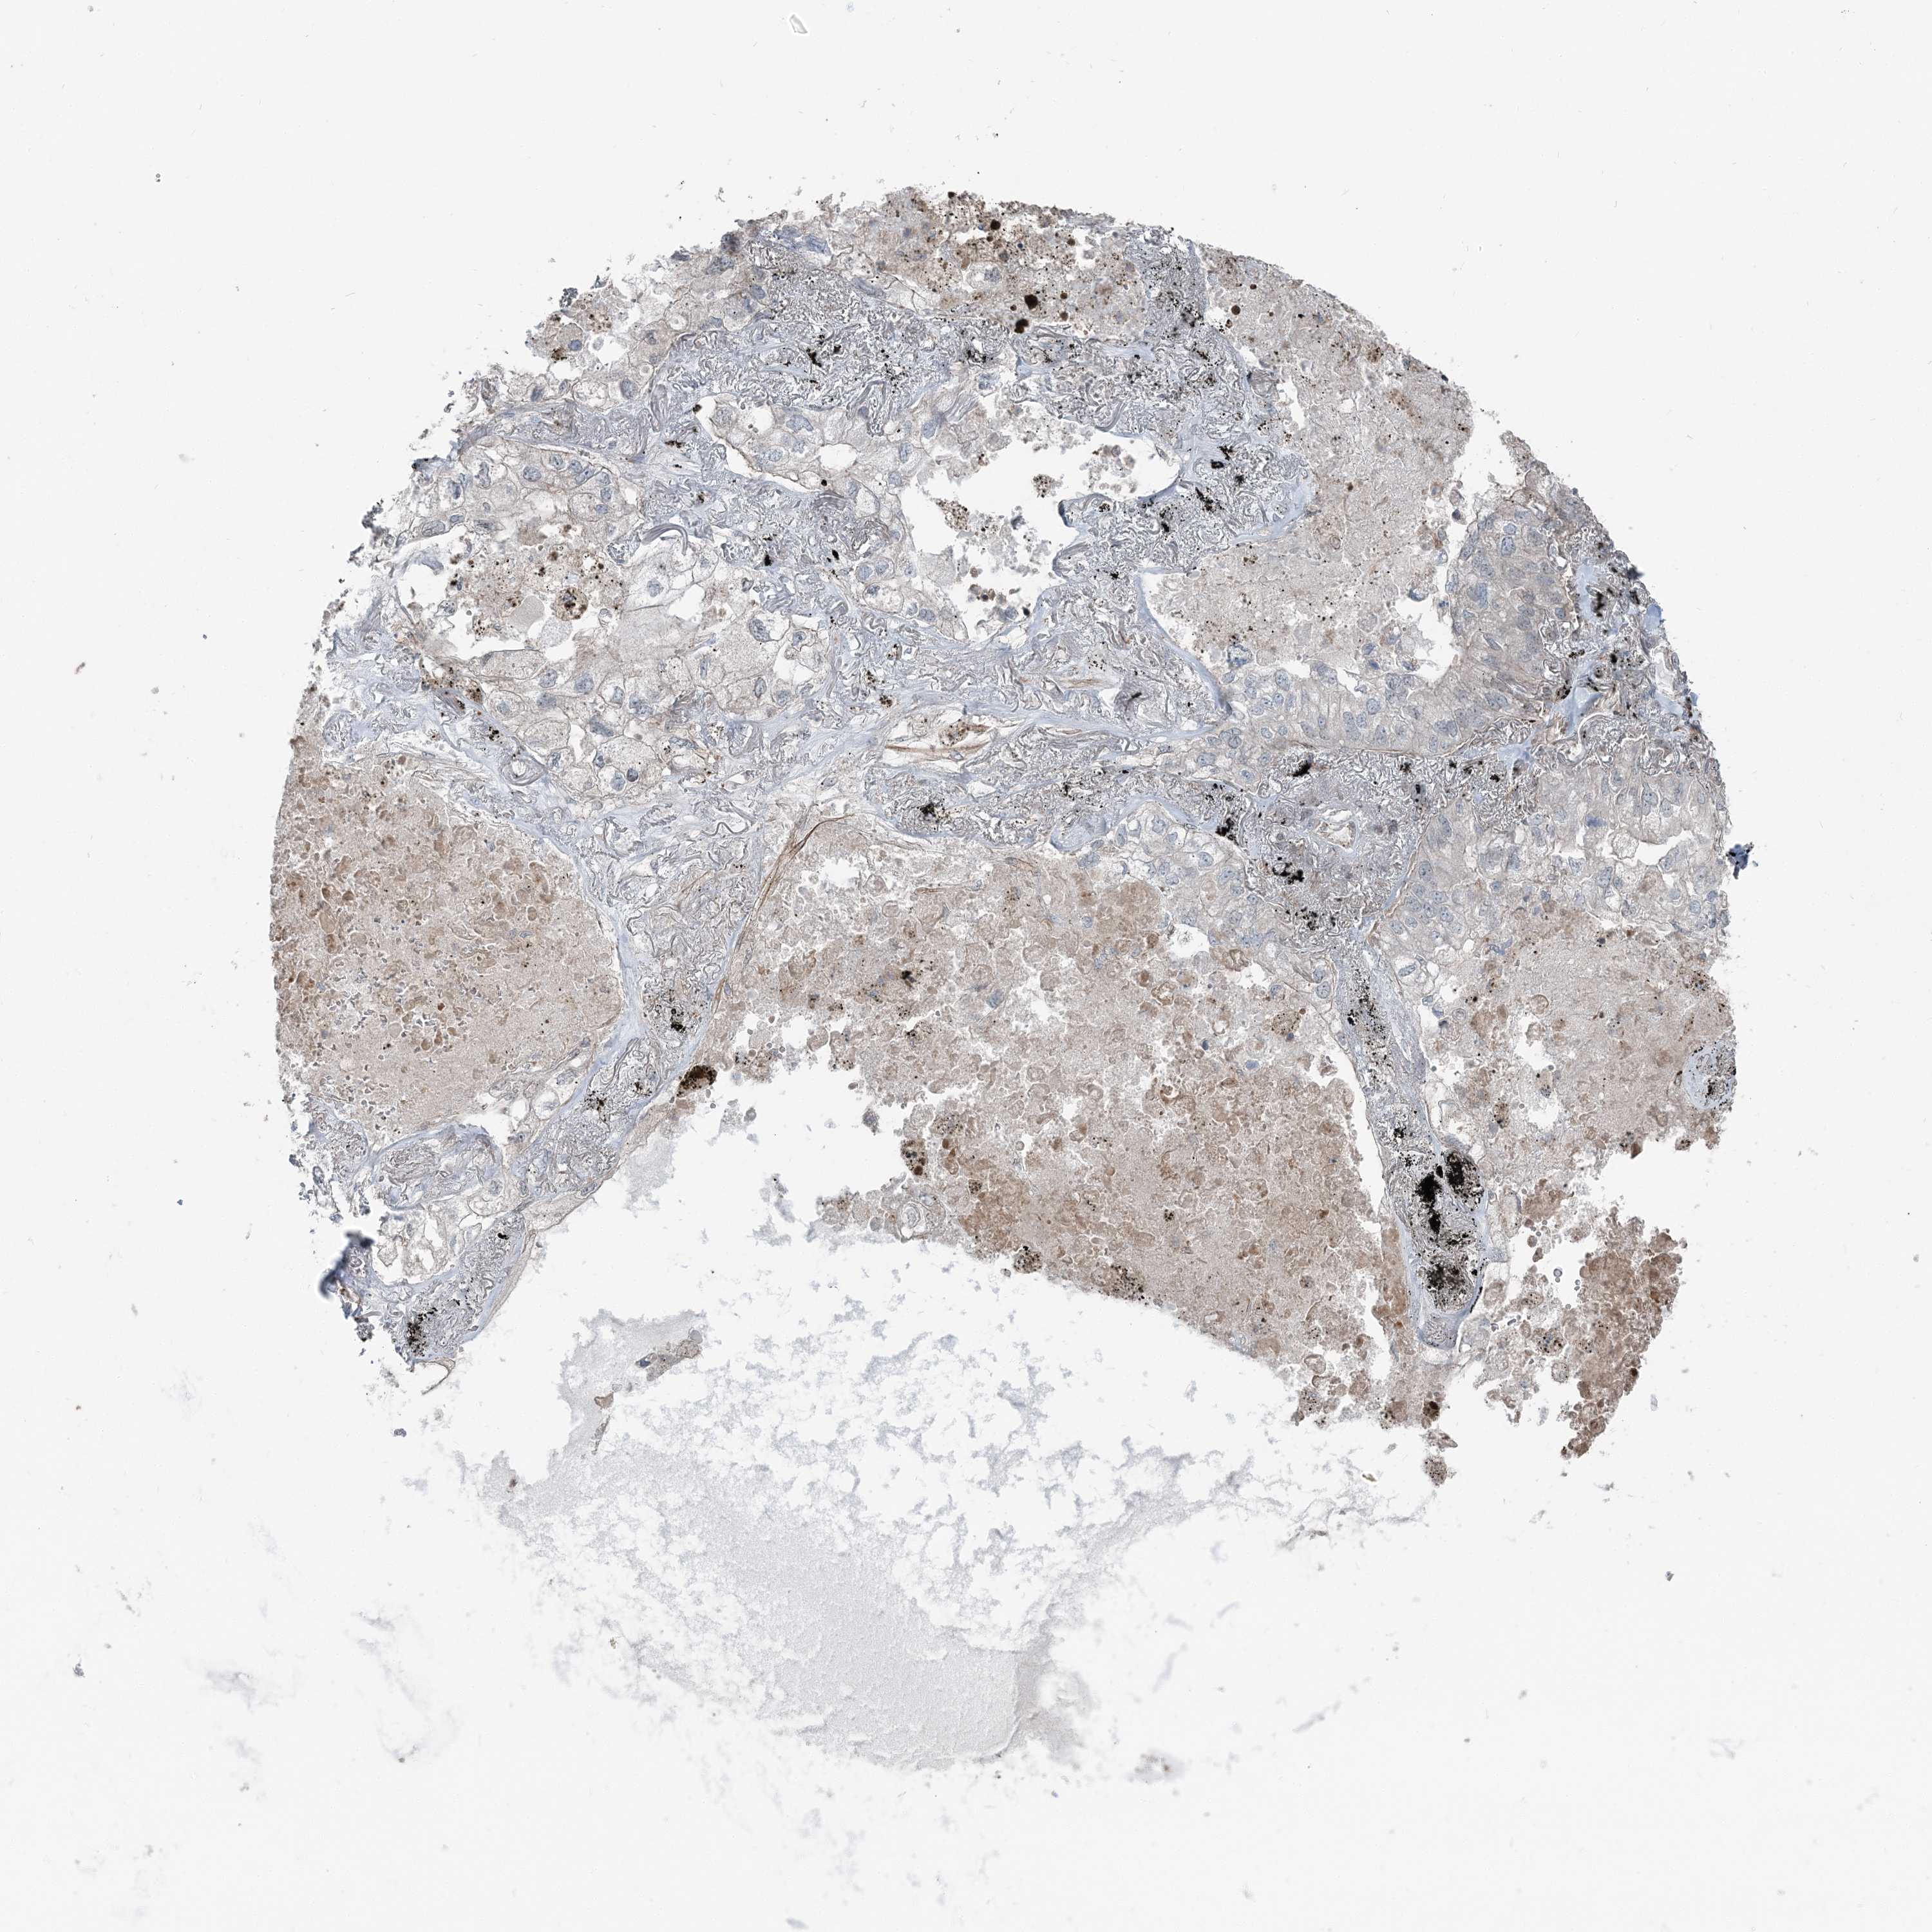

CANCER LUNG CANCER Show tissue menu

LUAD TCGA LUAD VALIDATION LUSC TCGA LUSC VALIDATION PROTEIN LUAD CPTAC PROTEIN LUSC CPTAC PROTEIN EXPRESSION

ANTIBODIES

AND

VALIDATION